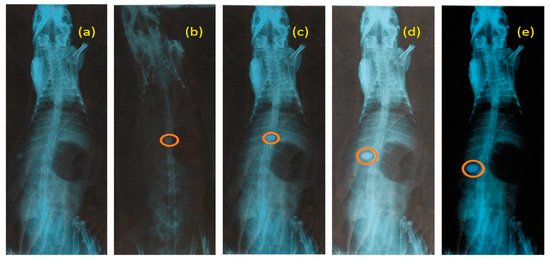

The mucoadhesion behavior of RGM-6 was observed in the rabbit stomach using the X-ray technique. The X-ray photograph was taken prior to the administration of formulation (Figure 9a). The next X-ray photograph was taken after 1hr of administration (Figure 9b). Obtained radiographic images at the end of 4 h revealed that the tablet was slightly altered in its position but remain adhesive to the mucosa. Swelling of the tablet visualized with a translucent swelling layer around it at the end of 8 h. Tablet was able to withstand the peristaltic movements of GIT, as it forms a strong disulfide bond with the mucus.

Figure 9.

X-ray radiograms (a) Before administering RGM-6, (b), (c), (d) and (e) showing mucoadhesion of RGM-6 at 1 h, 2 h, 4 h, and 8 h respectively.